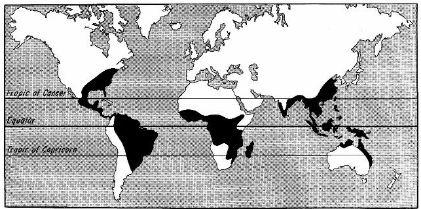

(hookworm) necator americanus

AKA new world hookworm

Distribution: Southern US, Appalachia

(hookworm) ancylostoma duodenale

aka old world hookworm

Not found in US but range overlaps with Necator americanus

strongyloides stercoralis

Wide distribution in the tropics and subtropics, extending into the moist temperate regions

In south US and Appalachia

100-200 million worldwide affected